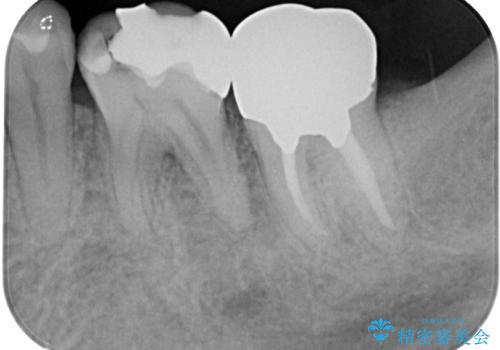

レントゲン写真などで診査を行ったところ、不適合な詰め物の周りから炎症が波及し、神経組織が壊死していると診断されました。

まずは根管治療を行い、症状が消退したことを確認してオールセラミッククラウンにて補綴治療を行うこととしました。